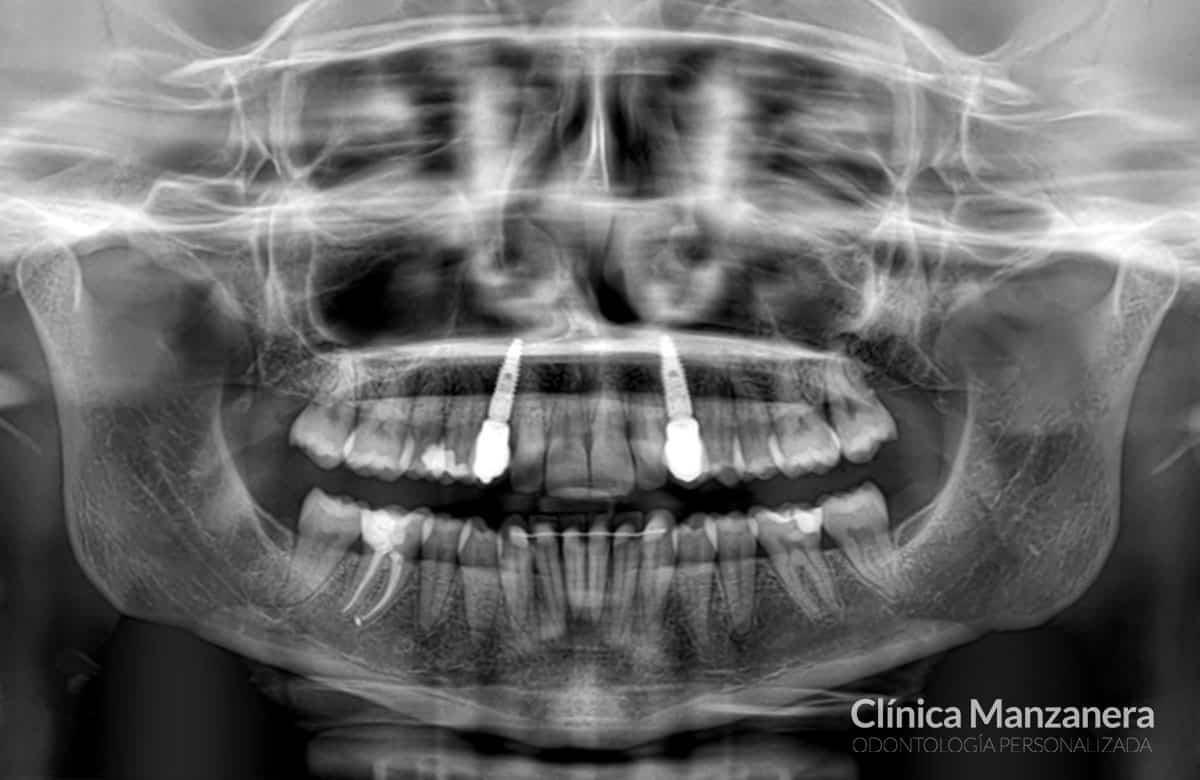

Implantes dentales

Implantes dentales en la zona de los caninos derecho e izquierdo, a cargo de la doctora Ester Manzanera.